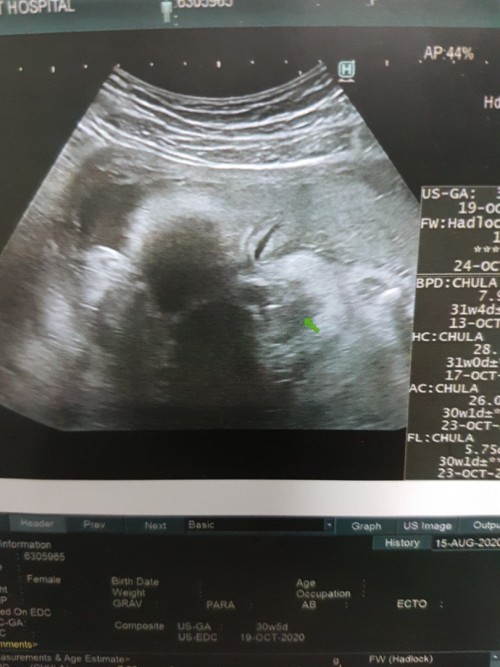

āđāļāđāļāļāļđ āļŦāļĨāļāļĨāļđāļ #āļāļāļāļđāđāļāļāļēāļ§āļāđāļāļĩāļĄāļāļļāļĨāļēāļŦāļāđāļāļĒāļāđāļ° ðĨ°ð§ļ